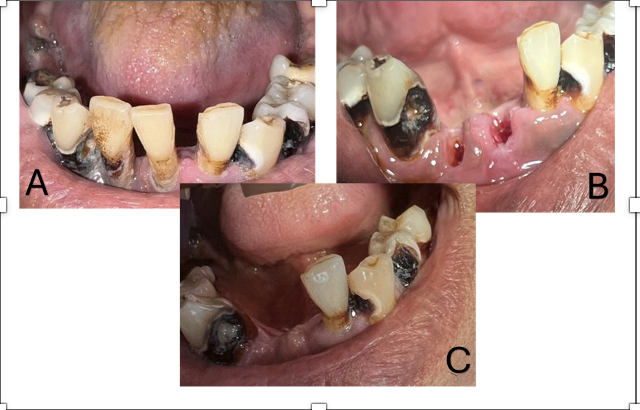

Periodontitis is one of the most common periodontal diseases affecting both elderly individuals and heavy smokers. This case report aims to describe the management of a geriatric patient with generalized chronic periodontitis and a history of heavy smoking. A 63-year-old male patient presented with a chief complaint of mobile teeth that had persisted for the past three months. Intraoral examination revealed necrosis, cervical caries, gingival recession, and poor oral hygiene. The treatment included extraction of the mobile teeth and socket curettage to remove necrotic tissue. The patient was prescribed antibiotics and analgesics, followed by a one-week post-operative evaluation. The patient reported no pain or swelling after extraction, and the healing process was satisfactory, with no signs of infection. The patient was also informed about a long-term treatment plan involving the fabrication of a prosthesis. Tooth extraction in patients with chronic periodontitis requires careful consideration of both clinical and non-clinical factors. This case highlights the importance of a comprehensive approach in the management of periodontitis in elderly heavy smokers.References